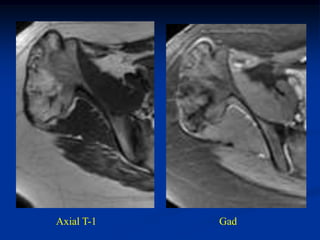

Case #608

17 year male with osteochondroma humerus

marrow

Axial T-1 MRI

cap

Sagittal T-1

MRI

Coronal T-2 MRI

Macro section